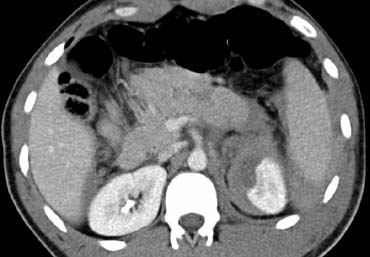

Ca lâm sàng 2

Cuộn qua các hình ảnh và mô tả các tổn thương.

Sau đó tiếp tục.

Các dấu hiệu bao gồm:

- Các vùng giảm tỷ trọng dạng tuyến tính phù hợp với vết rách lách.

- Các vùng giảm tỷ trọng hình tròn và bầu dục phù hợp với tụ máu trong lách.

- Tràn máu ổ bụng.

Tùy thuộc vào tình trạng lâm sàng, bệnh nhân này sẽ được điều trị bảo tồn không phẫu thuật, vì không có chảy máu hoạt động.